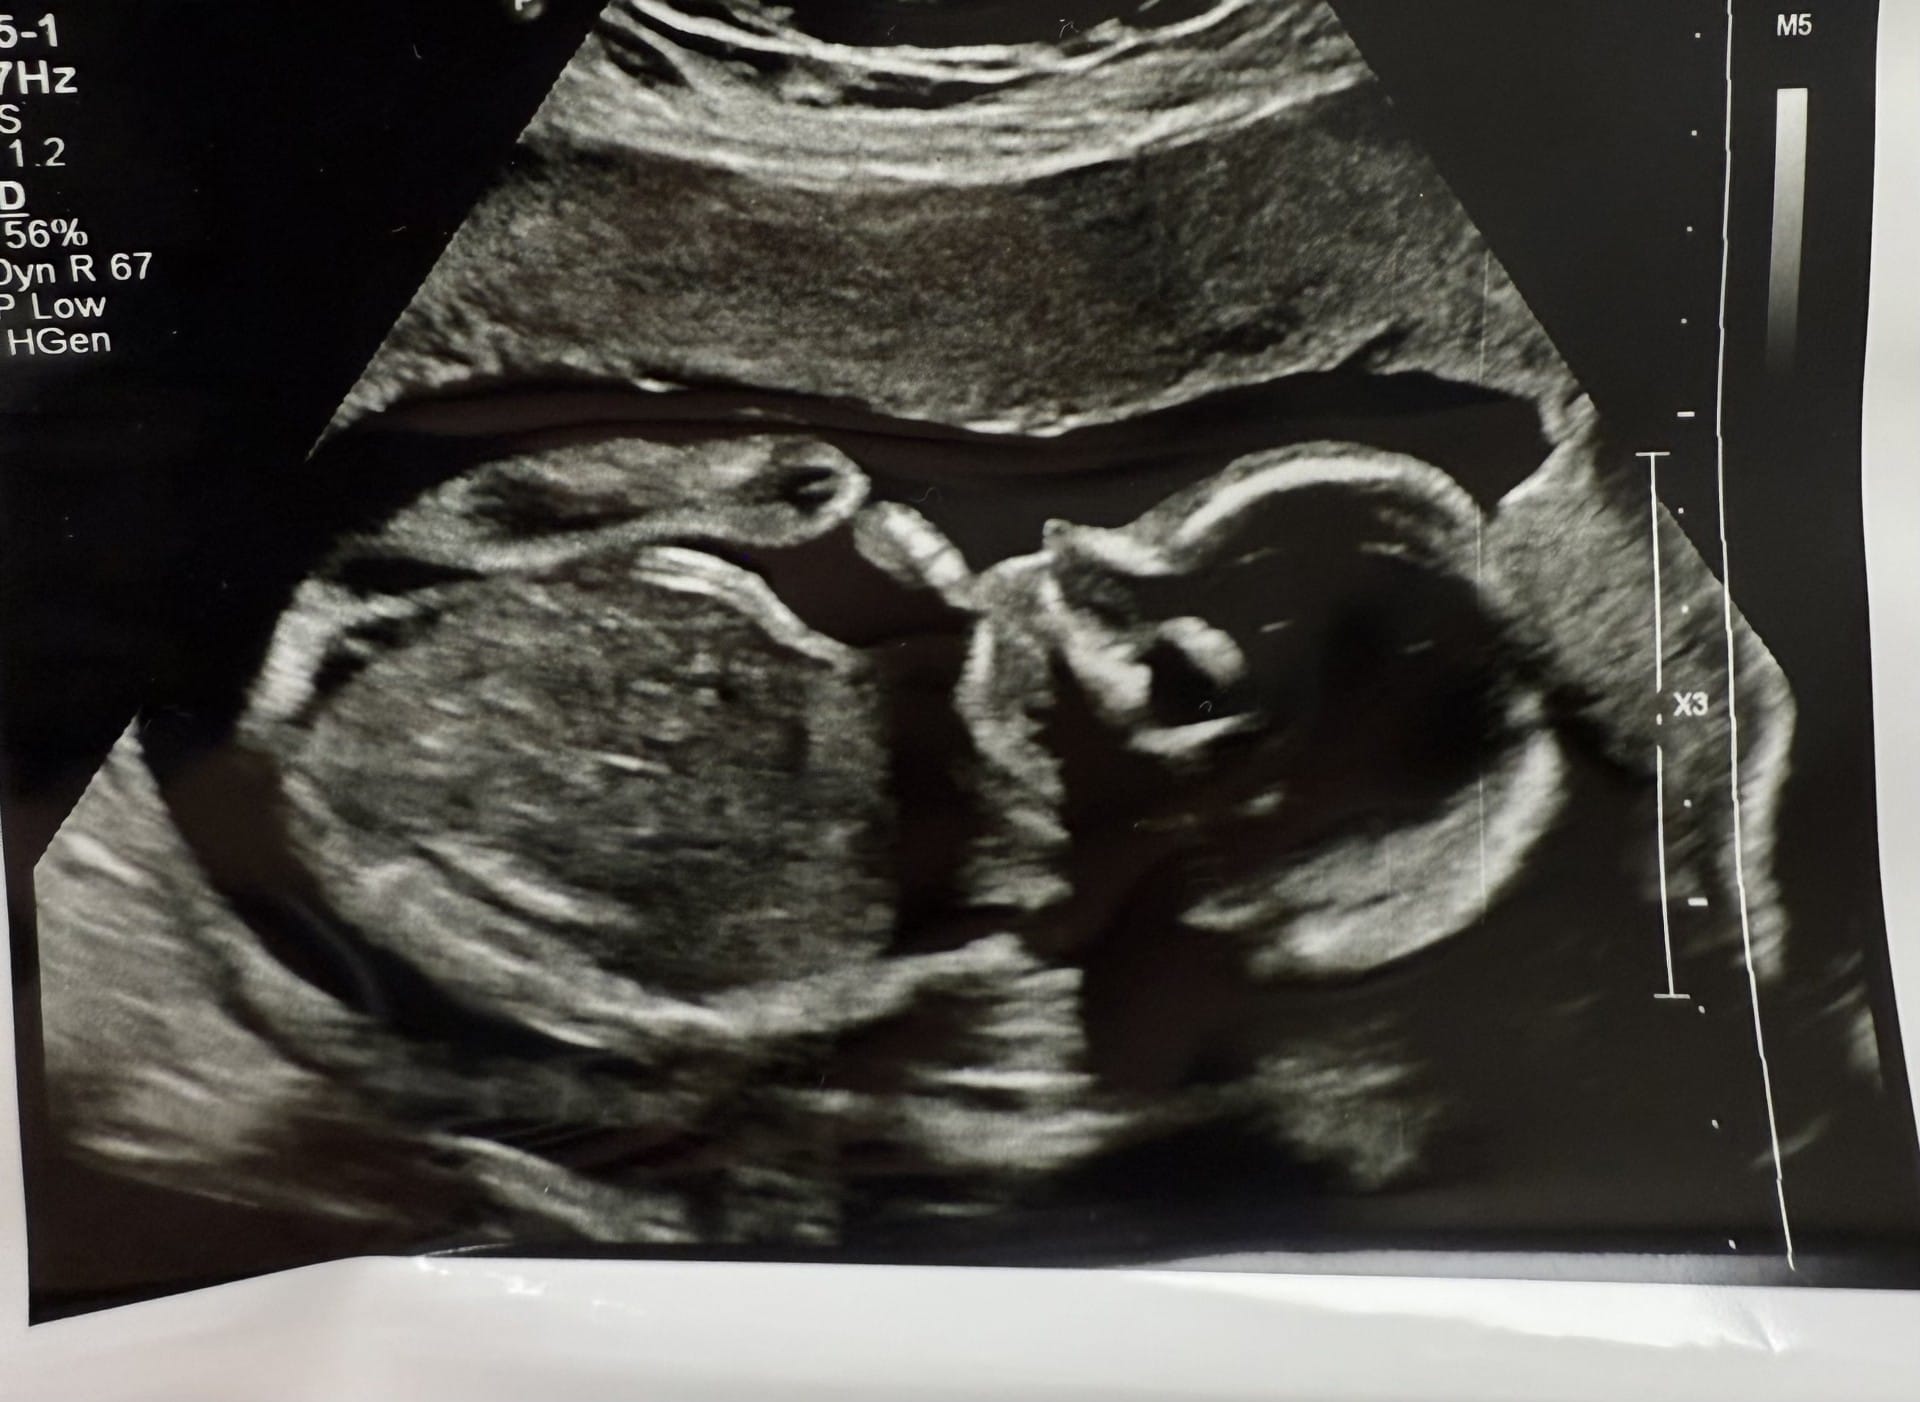

So as not to bury the lead, we will start with the exciting news... we are incredibly excited to share that we are expecting another child in February!

But the exact opposite happened. The doctor came in to confirm that Amanda was already pregnant!

She is now just over 20 weeks along and baby is looking happy and healthy and so are we! Amanda’s first trimester was pretty rough (which is why things have been a little more quiet from us, she typically does the talking!) but thankfully now in the second trimester she is feeling much better, if tired.